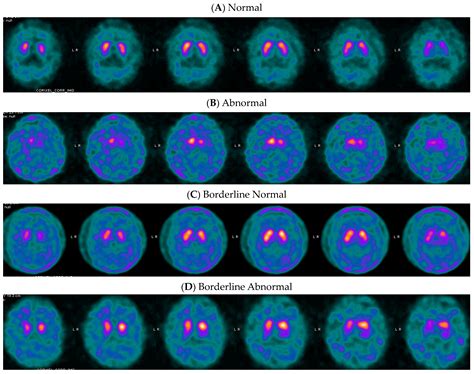

During the procedure, a small amount of a radioactive tracer is injected into the patient’s bloodstream. This tracer binds specifically to the dopamine transporters. Once the tracer has circulated, a specialized camera captures images that reveal how these transporters are distributed throughout the brain. A healthy scan shows a symmetric, comma-shaped appearance in the striatum, whereas a scan showing a reduction or distortion in these areas may indicate pathology.

The results of a Dat Scan are analyzed by a radiologist or nuclear medicine physician who assesses the density and distribution of the tracer. In patients with Parkinson’s disease, the imaging will typically show a significant decrease in the intensity of the signal in the striatum, often appearing as a loss of the "comma" shape.